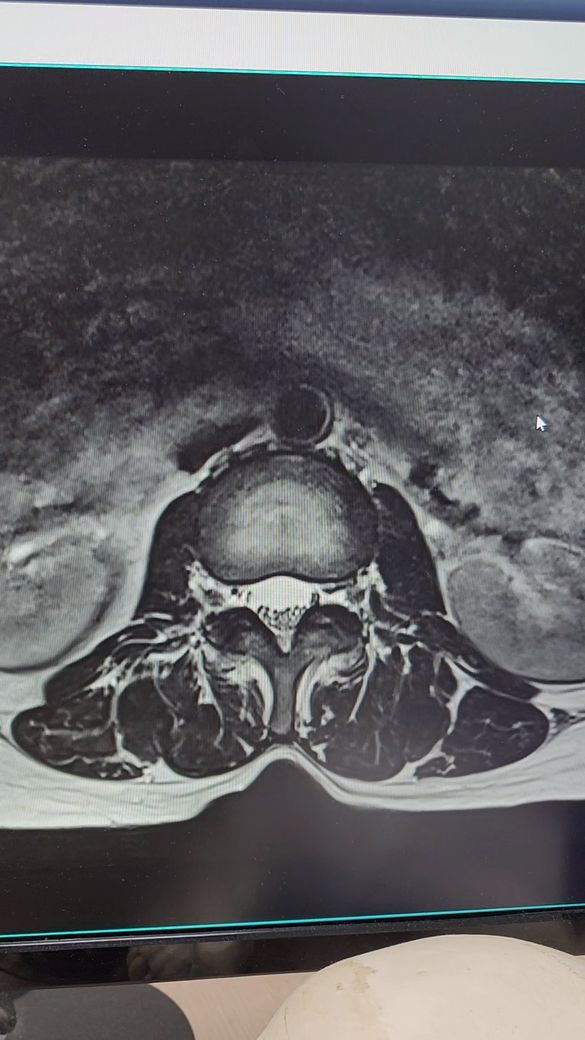

허리디스크 추간판탈출증.전방전위증

4월5일 척추,4.5번

추간판탈출증과 전방전위증으로 왼쪽 엉치부분과 사타구니 허벅지 뒷쪽 방사통과 다리저림이 심해요.처음엔 걷지도 못하고 한달반정도 물리치료,도수치료.약물치료하다가 좋아지질않아서